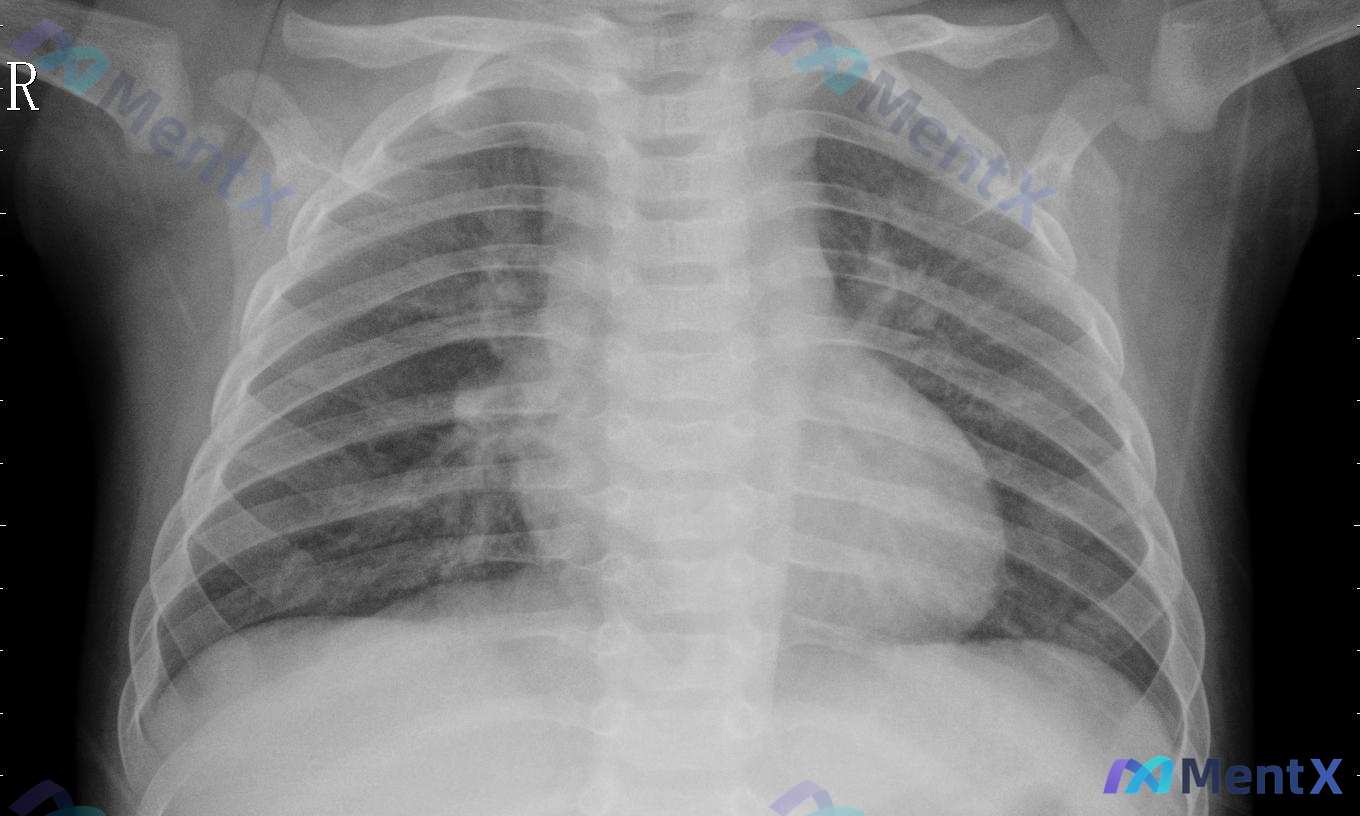

整理到一份儿童胸部X光的影像资料,先把核心客观信息放出来,大家第一眼思路会怎么排优先级? 基础信息 - 影像学提示为儿童患者(胸廓比例、骨骼发育形态) - 胸部前后位(AP)投照,吸气程度中等 主要影像表现 1. 气道纵隔:气管居中,心影大小正常范围 2. 肺野:双侧透亮度大致对称 - 右肺中下野:...